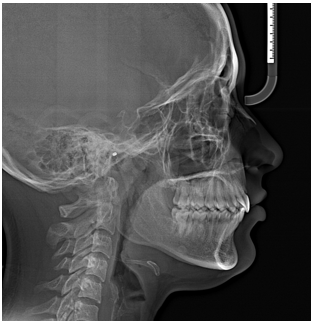

Positive changes were noted in both skeletal and dental parameters. The sagittal skeletal disparity showed enhancement, as indicated by the posterior shift of Point A and a decrease in the ANB angle by 3 degrees. Vertical angulation was slightly reduced further stating mandible undergoing forward auto-rotation and maxilla exhibiting intrusion.

Increase in the axial inclination of the maxillary anterior teeth expressed optimal torque articulation facilitated by the use of sequential archwires. Radiographic Analysis were used to measure molar distalization. ([Figure 6]).[11] The application of distalizing forces resulted in approximately 3.5mm disatlization of maxillary molar (measured from U6 to Pterigoid vertical and U6 to Facial axis). This was clinically verified by the transition from a full cusp Class II to a Class I molar relation. The lack of change in axial inclination was evidenced by the degree of tipping (α angle) and U6 to True Vertical Line (cusp tip and root apex) ([Table 1]).

Following the post-distalization phase, settling elastics were administered and adjusted in accordance with ABO (American Board of Orthodontics) guidelines. Subsequently, the orthodontic appliance was removed through the debonding process (Figure 7).